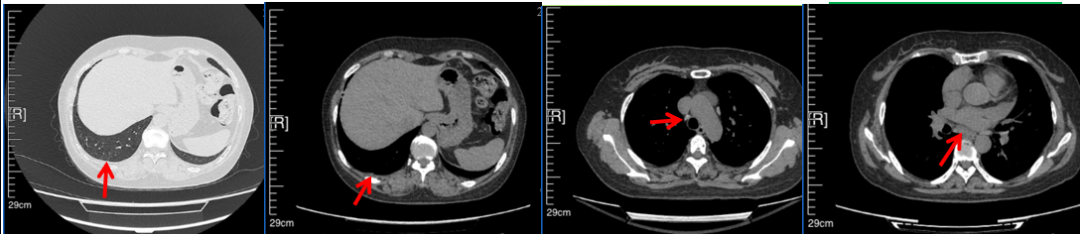

2016年1月复查CT提示支气管截断可见新发小结节,一线治疗采用培美曲塞+DDP方案化疗4周期(培美曲塞3.36,DDP 480mg)。化疗后复查胸部CT:右肺见不规则结节样影,最大层面大小约19mm*8mm,较前比较明显增大,疗效评估PD。2017.3-2017.4予单药多西他赛化疗3周期,疗效评估SD。2018年5月末复查CT提示结节较前增大,评效为PD,2018年6-10月予多西他赛+CBP化疗4周期,疗效评估SD。2022年5月患者出现活动后气短,复查胸部CT示右肺膨胀不良;右侧胸腔积液增多。胸腔积液包埋病理示符合肺腺癌细胞。行NGS基因检测:EML4:exon13-ALK:exon20融合。PD-L1(克隆号22C3)TPS<1%。

2018.07

2022.05

2022.08

2023.05

2024.12